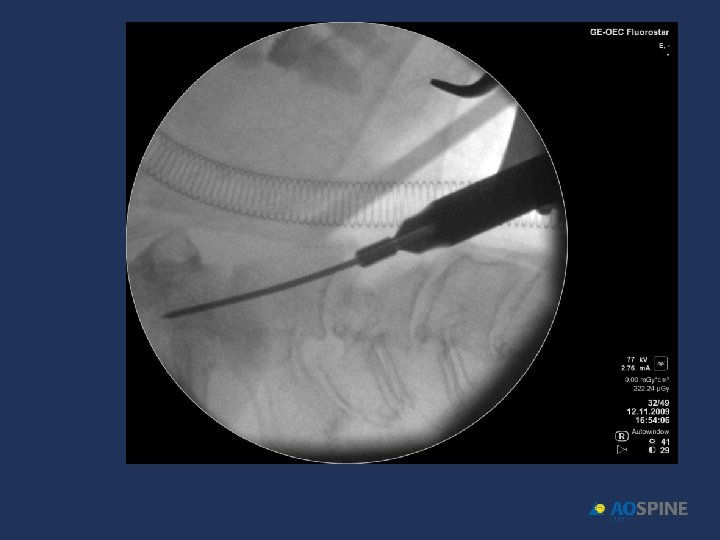

ODONTOID FRACTURES odontoid screw ADVANTAGES CONTRAINDICATIONS • PRESERVES MOTION C 1 C 2 • TRANSVERSE LIG RUPTURE • DONT NEED POSTOP HALO • EXTENSE C 2 BODY FX • DONT NEED BONE GRAFT • IRREDUCTIBLE FRACTURE • ANTERIOR OBLICUE FX

ODONTOID FRACTURES • RIGID COLLAR 10 -12 WEEKS • ONE SCREW • BEST RESULTS DURING FIRST 6 MONTHS AFTER FX Jenkins et al. J Neurosurg 1988, 89 Apfelbaum et al. J Neurosurg 2002, 93

ODONTOID FRACTURES odontoid screw • 90% FUSION TYPE II • 95% FUSION TYPE II < 6 MONTHS EVOL. • 100% FUSION TYPE III